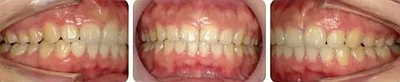

術(shù)后面型

正面觀反笑線糾正,閉口時唇肌自然。前突側(cè)面型得到改善。

術(shù)前術(shù)后側(cè)貌對比。